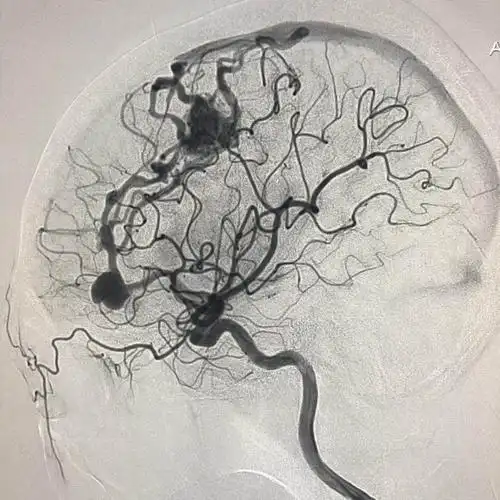

小脑血管畸形

脑中的不定时炸弹脑动静脉畸形

脑血管畸形通常因先天性脑血管发育异常所致,为脑出血常见原因之一

巨大脑血管畸形栓塞手术